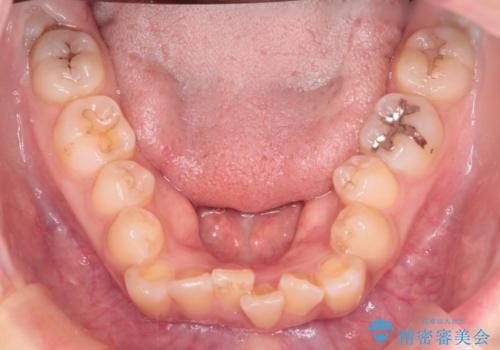

- 患者様は、歯並びのガタガタ(重度の叢生)を改善したいとのことで来院されました。診察すると、歯列のスペース不足が著しく、前歯が重なり合い、噛み合わせにも影響が出ている状態でした。歯をきれいに並べるためには抜歯によるスペース確保が不可欠と判断し、上下の小臼歯4本を抜歯したうえで、目立ちにくい審美ワイヤー矯正(白いワイヤーと透明ブラケット)を用いた治療計画を立てました。

抜歯によって歯を動かすためのスペースを確保。その後、審美ワイヤー矯正を用いて歯を1本ずつ適切な位置に誘導しながら、噛み合わせのバランスも整えていきました。時間はかかりましたが、ガタガタの歯並びがきれいに整い、機能的にも審美的にも満足のいく仕上がりとなりました。患者様からは「歯並びが劇的に改善し、見た目だけでなく噛みやすさも向上した」と喜びの声をいただきました。